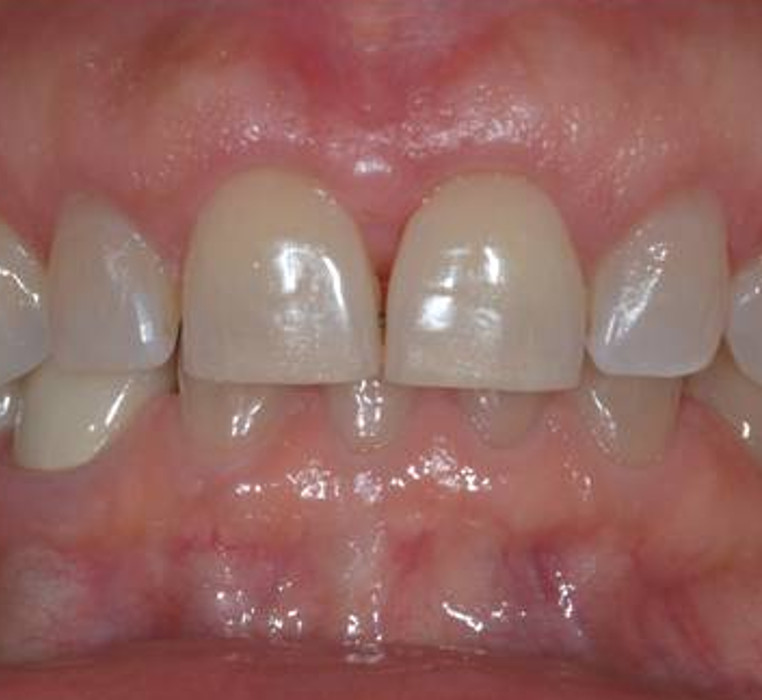

Ridge Augmentation (Gum and Bone) for a fixed bridge

Before